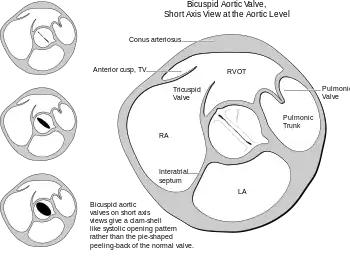

Transesophageal echocardiography- the right side commissure of the bicuspid aortic valve is ruptured

Heart bicuspid aortic valve diagram